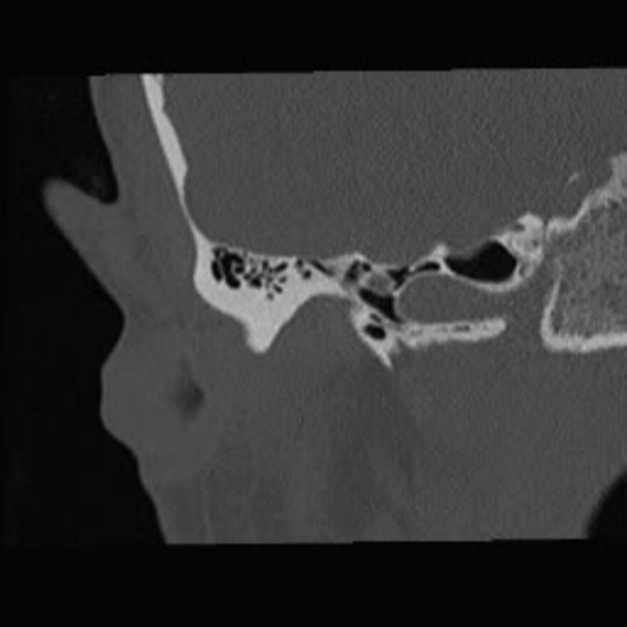

A 0.5-mm Coronal CT scan through the left temporal bone demonstrates ...

Computed tomography scan of temporal bone. Axial view at the level of ...

Axial high-resolution CT of the right temporal bone demonstrates ...

Axial computed tomogram (bone window) of temporal bone showing an ...